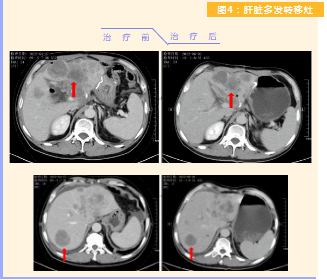

患者完成1周期治療后,上腹部疼痛癥狀基本消失,梗阻性黃疸癥狀緩解,腫瘤指標(biāo)下降(圖1),肺部多發(fā)轉(zhuǎn)移灶消失和縮小(圖2),雙肺門淋巴結(jié)縮小(圖3),肝臟多發(fā)轉(zhuǎn)移灶縮小(圖4)。